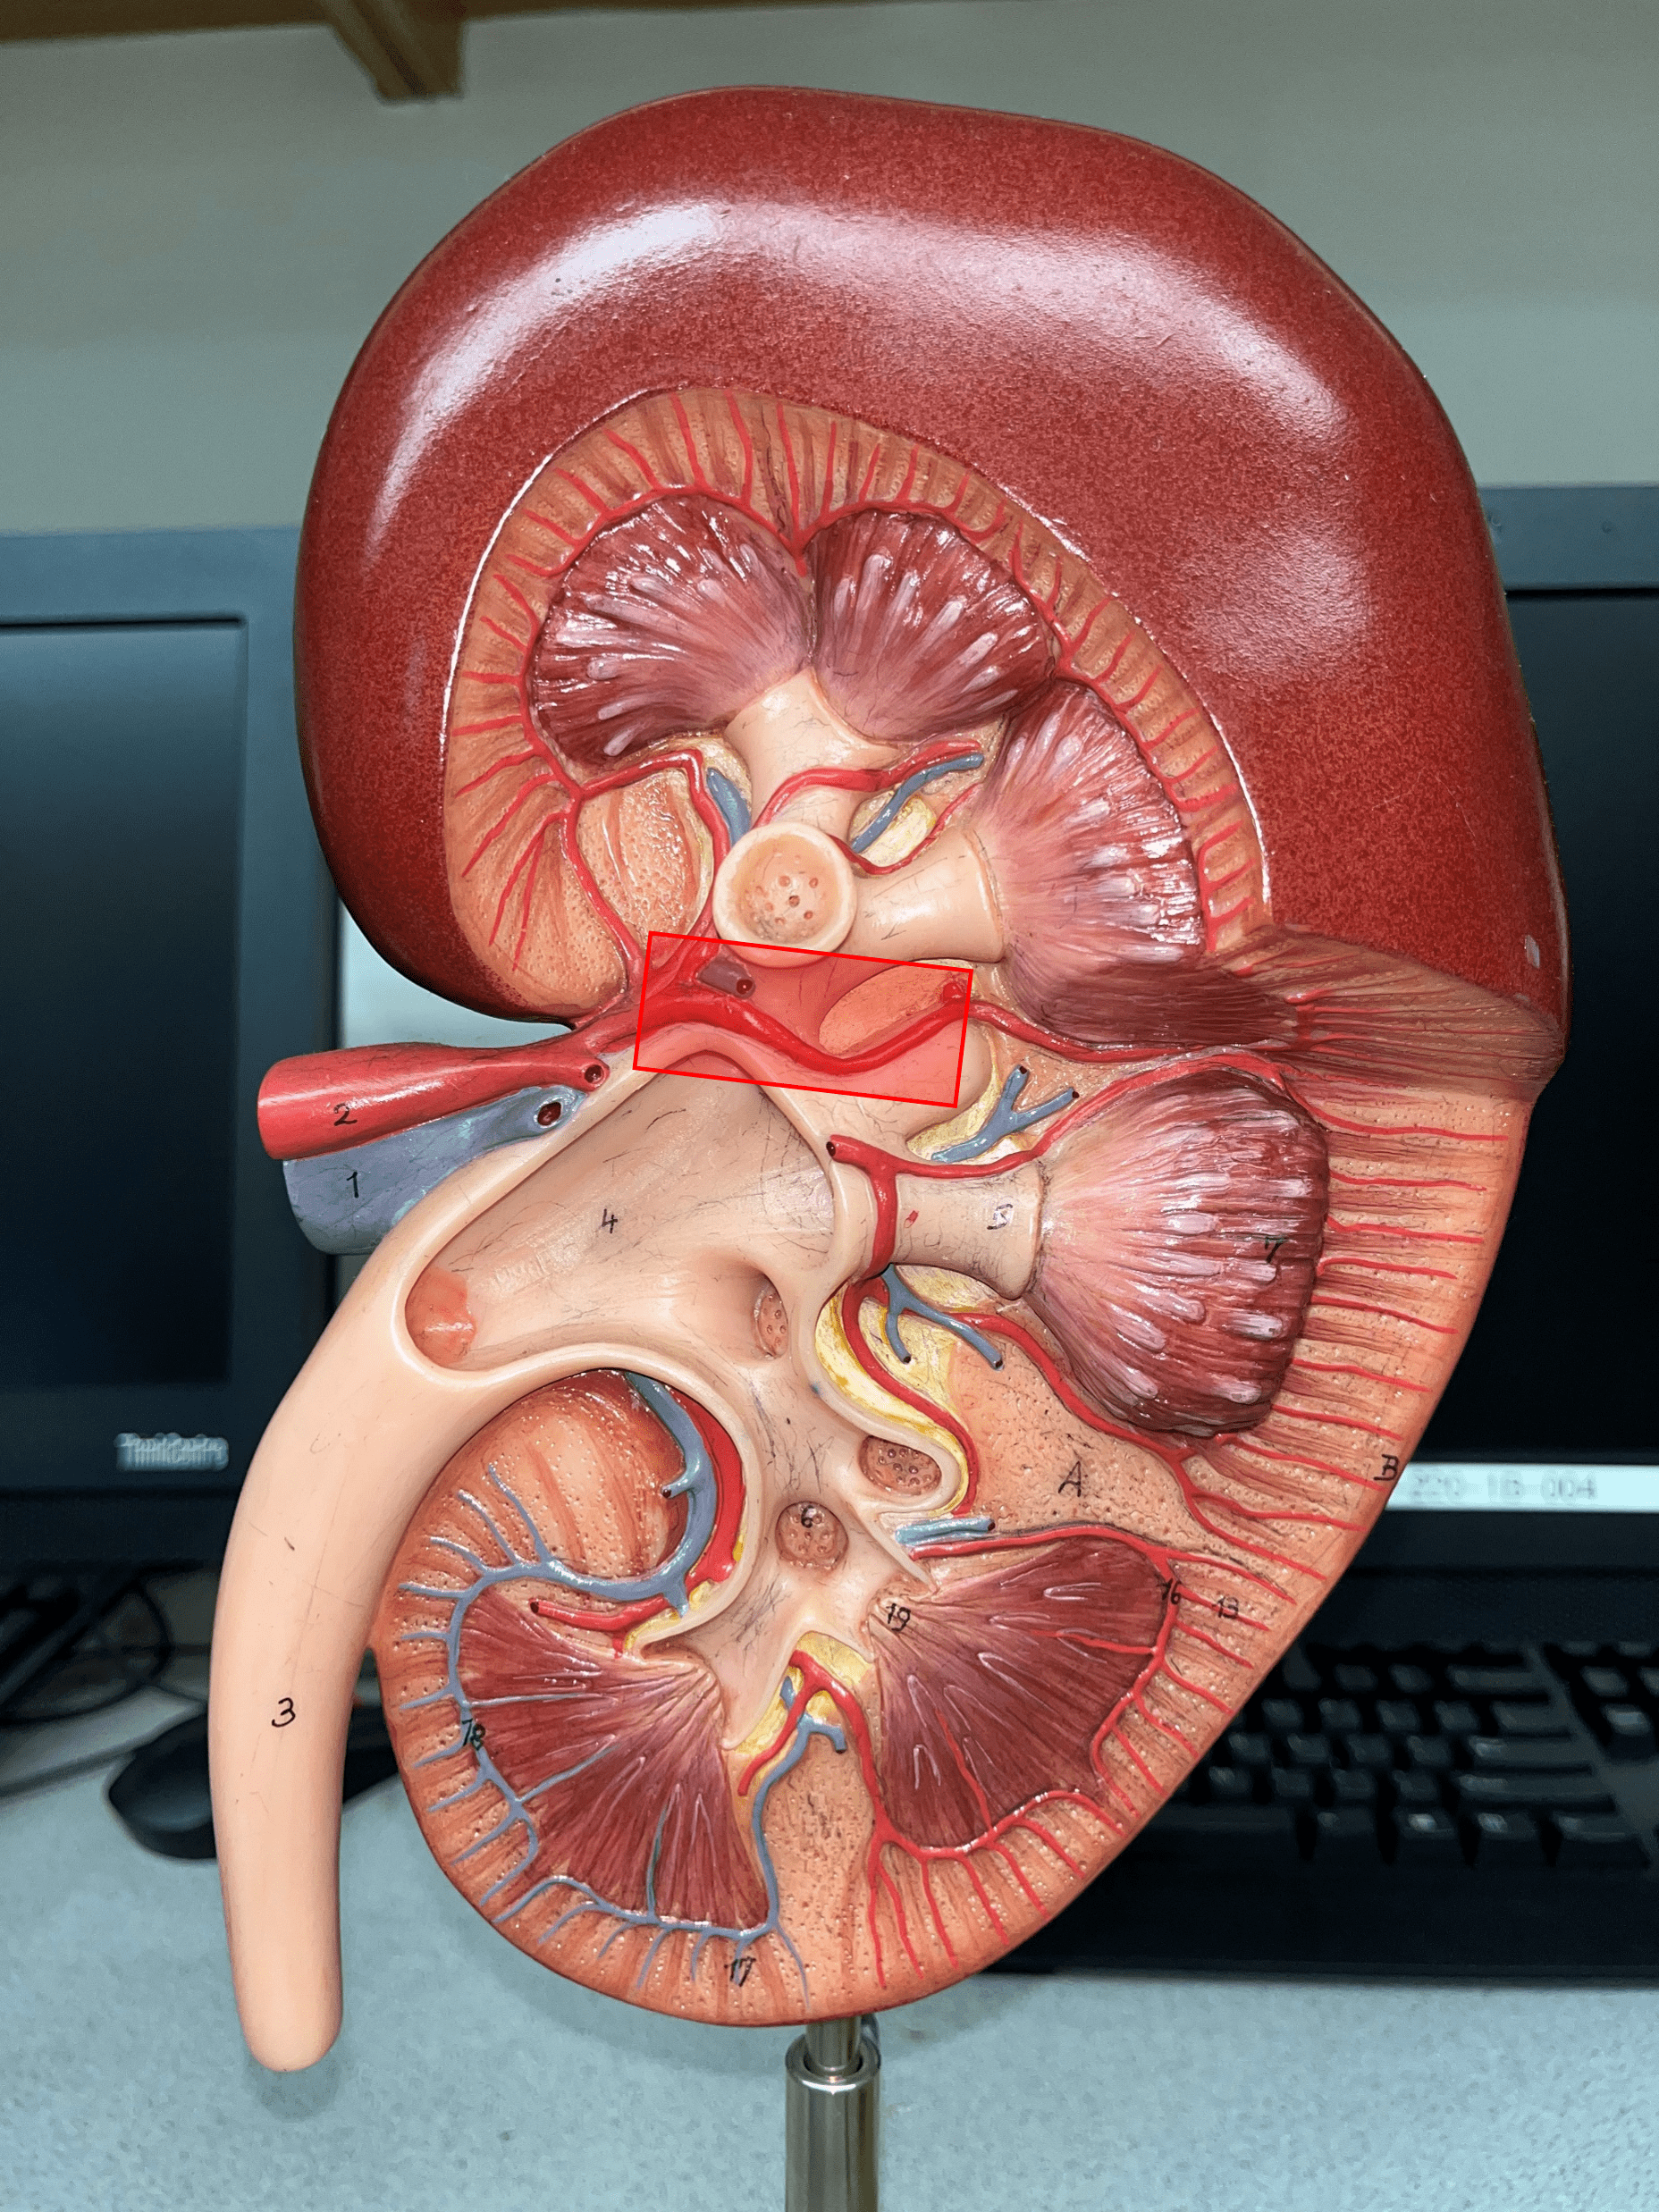

minor calyx

• A cup-like extension that collect urine from the renal papilla.

• Converges with others to form a larger major calyx.

• Converges with others to form a larger major calyx.

major calyx

• The convergence of several minor calyces.

• Drains into the renal pelvis.

• Drains into the renal pelvis.

renal pelvis

• The innermost region of the internal kidney.

• Collects urine from the major calyces and drains it into the ureters.

• Includes the minor and major calyces.

• Collects urine from the major calyces and drains it into the ureters.

• Includes the minor and major calyces.